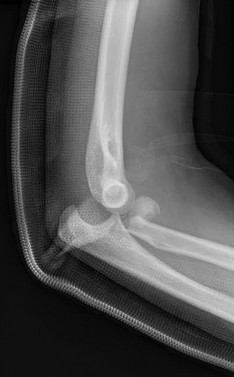

Question 13:

A 6-year-old boy sustains a severe extension-type supracondylar humerus fracture after a fall. Radiographs classify it as a Gartland Type III. The distal fragment is severely displaced posteromedially relative to the proximal shaft. Based on this specific displacement pattern, which of the following nerve structures is at greatest risk of tethering or injury from the proximal fragment?

Correct Answer: Radial nerve

Explanation:

In an extension-type supracondylar humerus fracture, the displacement of the distal fragment dictates the direction of the proximal spike. If the distal fragment is displaced posteromedially, the sharp proximal fragment is thrust anterolaterally, placing the radial nerve at the highest risk of injury. Conversely, if the distal fragment displaces posterolaterally, the proximal spike goes anteromedially, placing the median nerve (and AIN) at greatest risk.

A 45-year-old male sustains the injury pattern depicted in the provided image. During surgical reconstruction of the lateral collateral ligament complex, identifying the correct isometric origin of the lateral ulnar collateral ligament (LUCL) on the distal humerus is critical. Where is this point located?

Correct Answer: At the center of the axis of rotation of the capitellum

The isometric point for the LUCL origin on the humerus is the center of the axis of rotation of the capitellum. Placing a graft or suture anchor at this specific geometric location ensures that the reconstructed ligament maintains relatively constant tension throughout the elbow's entire arc of flexion and extension.